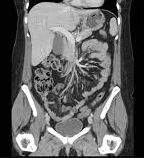

A complete history and physical examination are necessary for early diagnosis and treatment. X-ray; magnetic resonance imaging (MRI); computed tomography (CT) scan; ultrasonography; blood studies; tumor markers; tissue biopsy and tumor staging may be required.